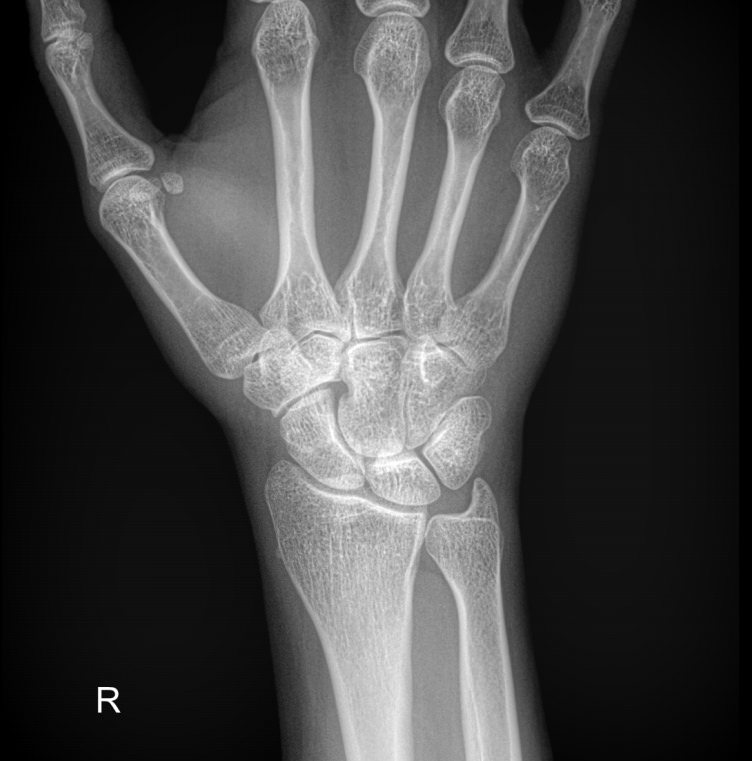

Самым первым исследованием запястья, наряду с лабораторными анализами, обычно является рентген. Это распространенный, простой в проведении и быстрый в получении результатов, а также высоко информативный для всей костной системы метод. В настоящее время он стал и практически безопасным в плане облучения: количество испускаемых лучей минимально и позволяет выполнять рентгенодиагностику несколько раз в год, не набирая при этом максимально допустимой дозы.

Что показывает рентген лучезапястного сустава

• Взаимоотношения суставных поверхностей ― в норме или вывих;

• Состояние суставной щели ― в норме, сужена, есть ли выпот и обызвествление капсулы;

• Состояние суставных поверхностей ― эрозии или ровный контур;

• Структура костной ткани ― типична, остеопения, деструкция или другие патологии;

• Переломы, трещины, костные обломки;

• Изменения в мягких тканях;

• Новообразования.